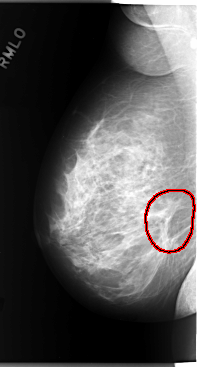

C_0101_1.LEFT_MLO

FILE: C_0101_1.RIGHT_CC.OVERLAY

TOTAL_ABNORMALITIES 1

ABNORMALITY 1

LESION_TYPE MASS SHAPE ARCHITECTURAL_DISTORTION MARGINS SPICULATED

ASSESSMENT 5

SUBTLETY 5

PATHOLOGY MALIGNANT

TOTAL_OUTLINES 1

BOUNDARY